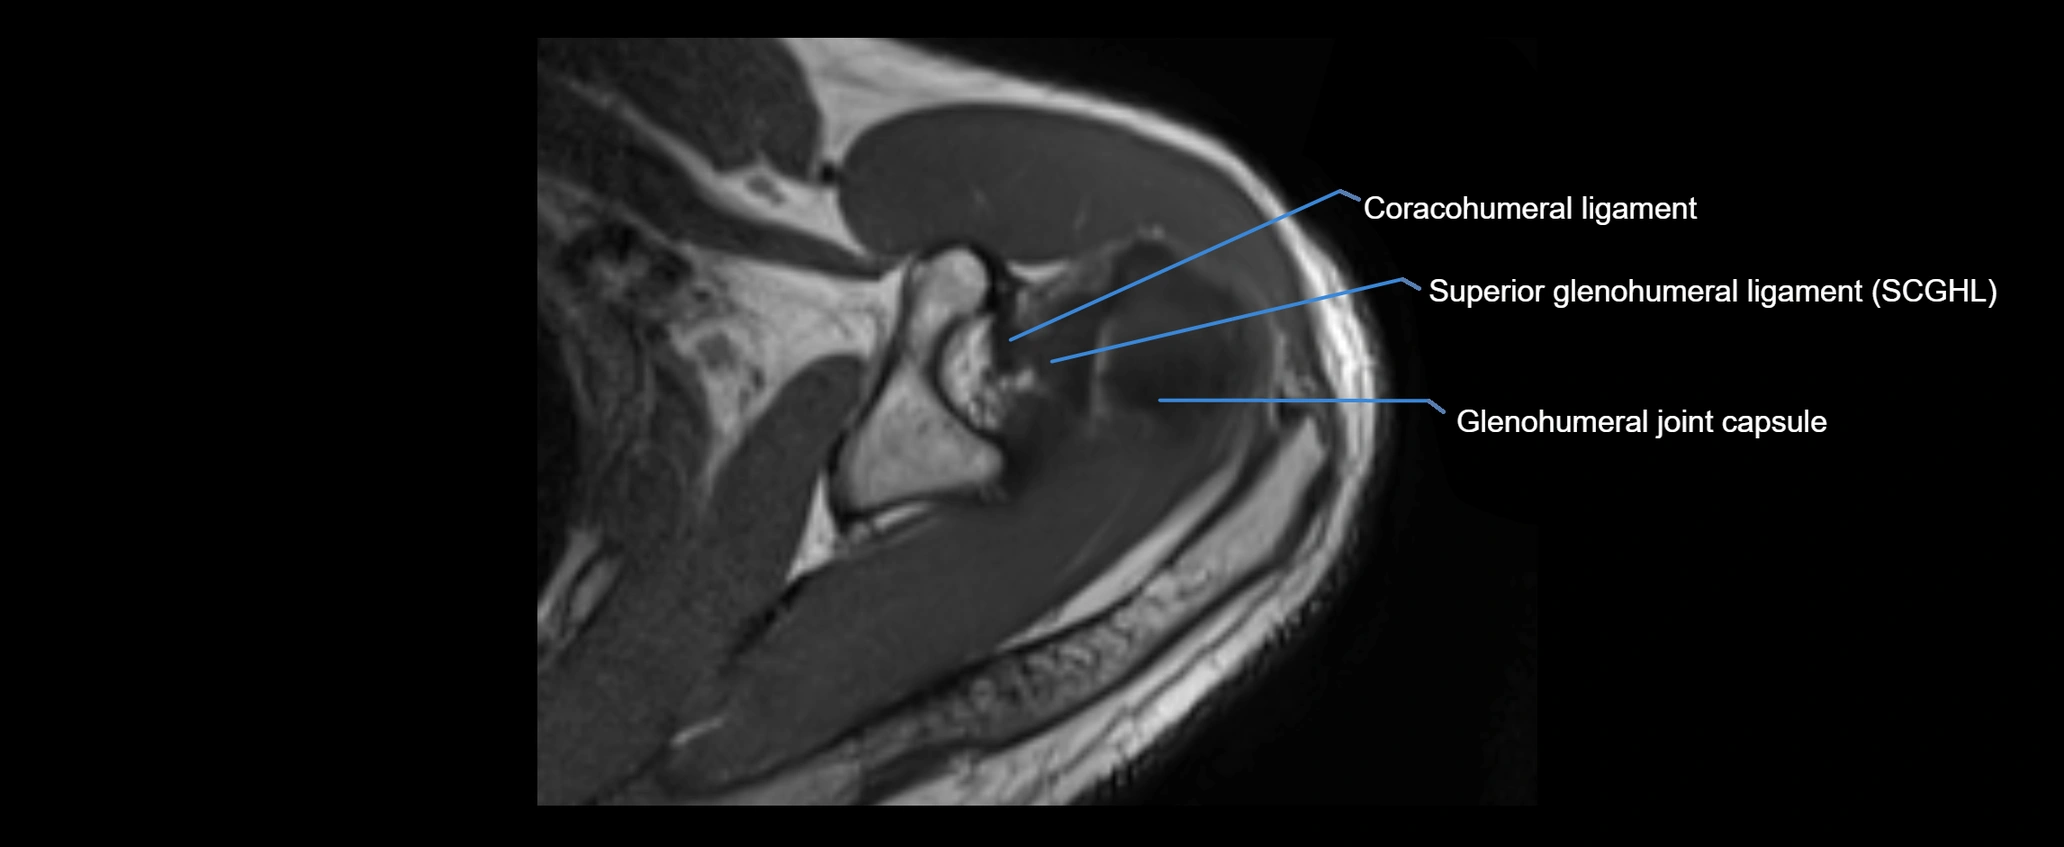

MRI images

image